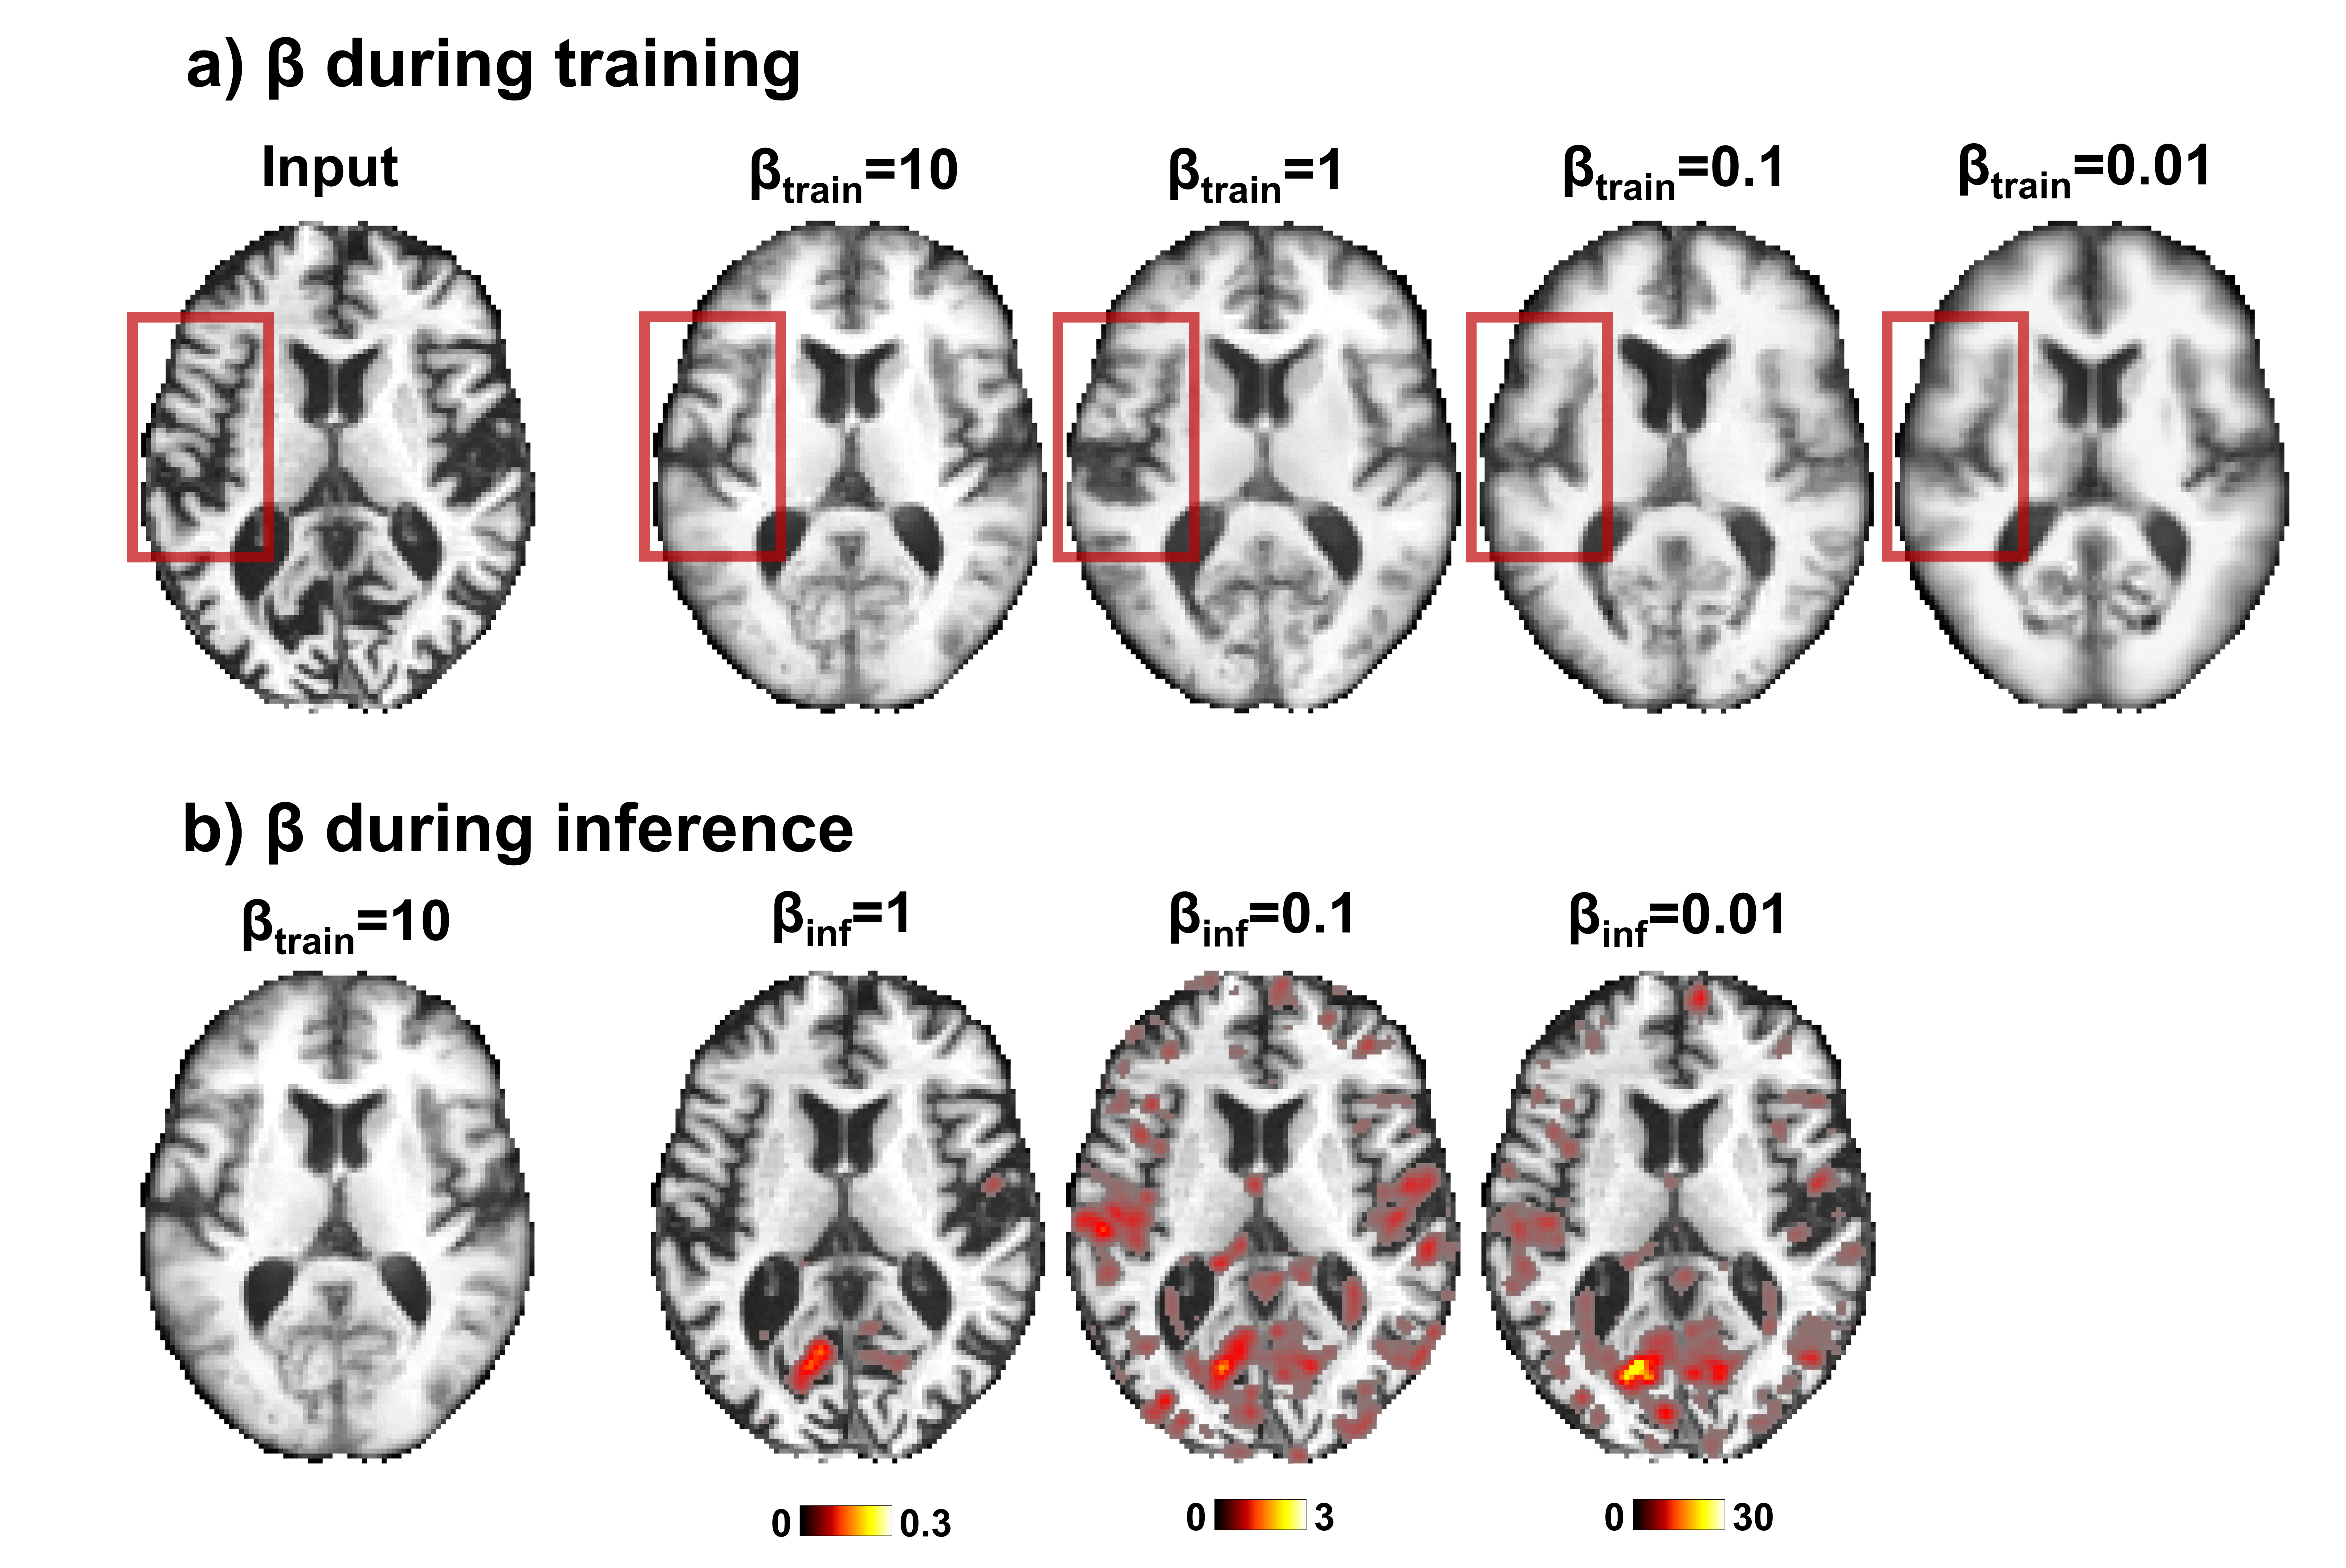

We next evaluate the ability of our method to determine the severity of the localized anomalies by comparing our anomaly maps to medial temporal lobe atrophy (MTA) scores [20] that were assessed by a senior board-certified neuroradiologist. These scores range from 0 to 4 and are assigned based on the degree of structural changes observed in the choroid fissure, the temporal horn of the lateral ventricle, and the hippocampus. Fig. 4 shows a visual correlation between the degree of atrophy highlighted in the anomaly map in these key regions and the MTA scores, demonstrating the utility of our method in determining the severity of detected anomalies.